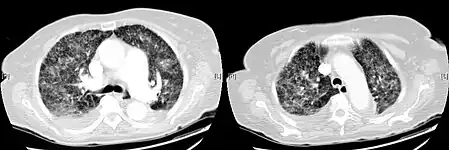

X-ray, showing extensive bilateral reticulo-nodular infiltrates -

Miliary tuberculosis is a form of tuberculosis that is characterized by a wide dissemination into the human body and by the tiny size of the lesions (1–5 mm). Its name comes from a distinctive pattern seen on a chest radiograph of many tiny spots distributed throughout the lung fields with the appearance similar to millet seeds—thus the term "miliary" tuberculosis. Miliary TB may infect any number of organs, including the lungs, liver, and spleen.[5] Miliary tuberculosis is present in about 2 percent of all reported cases of tuberculosis and accounts for up to 20 percent of all extra-pulmonary tuberculosis cases.[6]

Testing for miliary tuberculosis is conducted in a similar manner as for other forms of tuberculosis, although a number of tests must be conducted on a patient to confirm diagnosis.[7] Tests include chest x-ray, sputum culture, bronchoscopy, biopsy, CT/MRI, blood cultures, fundoscopy, and electrocardiography.[1] The tuberculosis (TB) blood test, also called an Interferon Gamma Release Assay or IGRA, is a way to diagnose latent TB.A variety of neurological complications have been noted in miliary tuberculosis patients—tuberculous meningitis and cerebral tuberculomas being the most frequent. However, a majority of patients improve following antituberculous treatment. Rarely lymphangitic spread of lung cancer could mimic miliary pattern of tuberculosis on regular chest X-ray. [14][4]